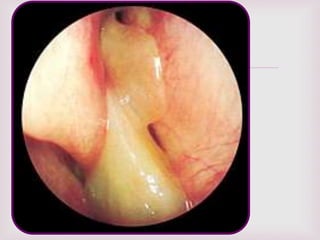

EXPLORACIÓN FÍSICA.

 Tumores con aspectos de uva.

 Se pueden encontrar en ambas fosas

nasales.

 Pueden adoptar la forma de la región

anatómica donde se encuentran.

 Blandos, tersos, translucidos.

 Ulceraciones con sangrado en ocasiones.

 Se encuentran en la parte superior de la

cavidad nasal y proceden del complejo

osteomeatal.

 La rinoscopia anterior

confirmara la presencia

de pólipos.

 Características macroscópicas de

los pólipos nasales…